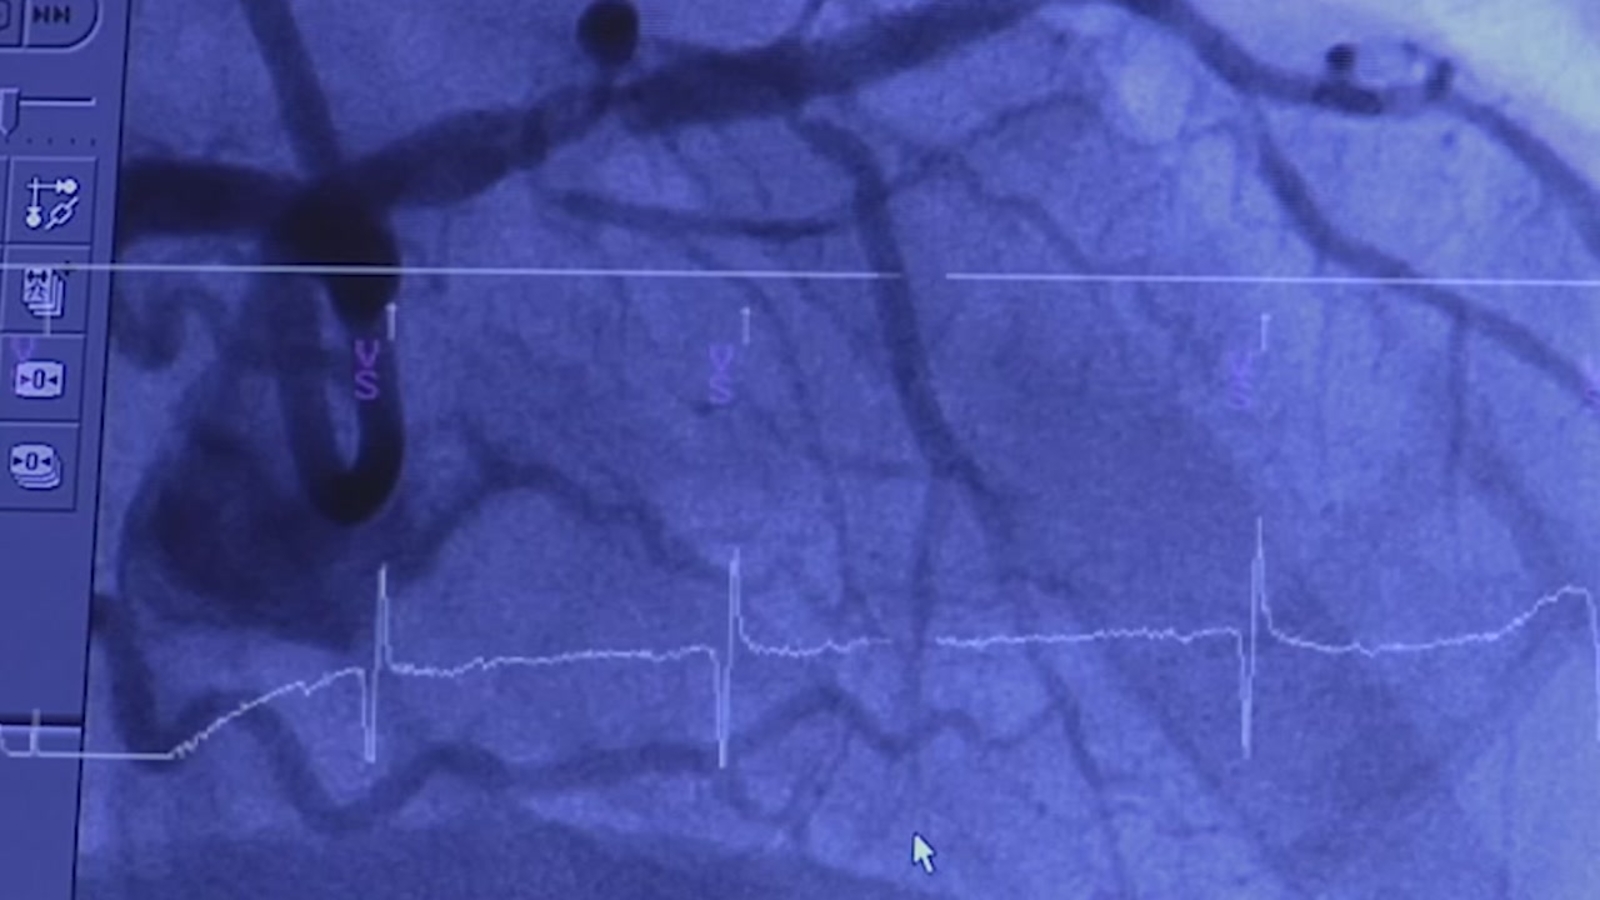

Hower says she'd been running and exercising for most of her life, until doctors discovered a dangerous inherited condition called cardiomyopathy, which diminishes the hearts ability to pump blood. What they couldn't tell her was the exact cause, or whether she might pass it down to her children.

It gives doctors at Stanford the power to sequence and search a patient's entire genome, for clues to the cause of their disease. The difference between looking at a handful of genes, versus some 20,000. He says in many cases, the answers can lead to life changing treatment.